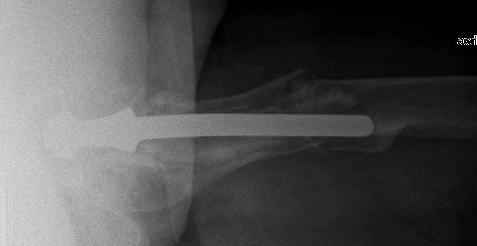

Female, rheumatoid, THA in 2003, car accident in 2006, failed plating. Nailing in Oct 2007. The nail is solid with hollow proximal part where the stem is docked. Last images are in 1 year after

nailing.